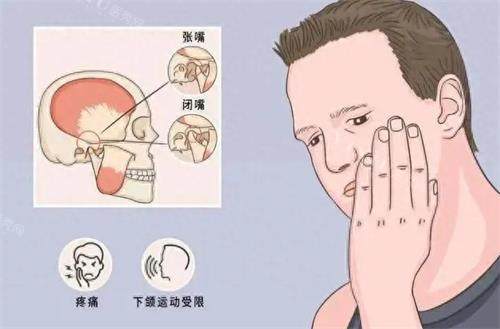

我的牙齿问题属于“骨性前突+深覆合”,上牙外飘,下巴后缩,侧面看像“月亮脸”。20岁出头时就想矫正,但被“钢牙妹”的标签劝退。直到去年刷到同事在天天有口腔做隐形矫正的实例,她摘下牙套后脸型变精致了,我才重新燃起希望!

接待我的是黄玲玲医生,她先让我填了一份详细的口腔健康问卷,又用一台“黑科技仪器”(后来才知道是iTero口扫仪)在嘴里扫了5分钟,电脑屏幕上立刻出现了我的3D牙齿模型!黄医生指着屏幕说:“你看,你的上颌骨发育过度,牙齿拥挤导致咬合错位,需要通过拔牙+隐形矫正内收前牙。”

深覆合改善,咬合关系修复正常